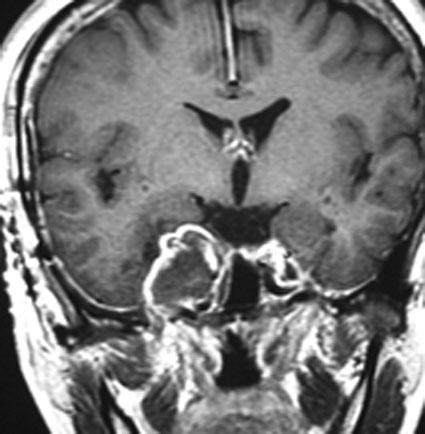

左上顎癌と間違えそうなMRI画像です。CTでは左の正円孔(黄色の矢印)が辺縁が滑らかに拡大 erosion しているので三叉神経第2枝(上顎神経)の神経鞘腫の診断がつきます。

メッケル腔(ガッセル神経節)という場所から発生した三叉神経鞘腫のMRIです。サイズは放射線治療するには大きすぎます。ですから手術摘出します。手術には側頭開頭硬膜外法と経鼻内視鏡手術があります。内視鏡手術は三叉神経が外側に来ているので優位性があります。開頭手術では,側頭部の前の方を小さく開頭して脳の硬膜の外から腫瘍を見るだけで取れます。もちろん脳の損傷は起こさないようにしなければなりません。手術中には三叉神経が薄く広がって腫瘍のまわりにくっついていますからそれを大事に守りながら腫瘍を取っていきます。

手術のすぐ後のMRIです。幸いなことにこの患者さんでは,腫瘍を全部取ったのですが三叉神経の大部分を残すことができて,顔のしびれはとても軽くてすみました。全摘出すると経鼻手術でも開頭手術でも多少の顔面の痺れ(感覚低下)はでますが,日常生活に支障のないレベルに留めなければなりません。